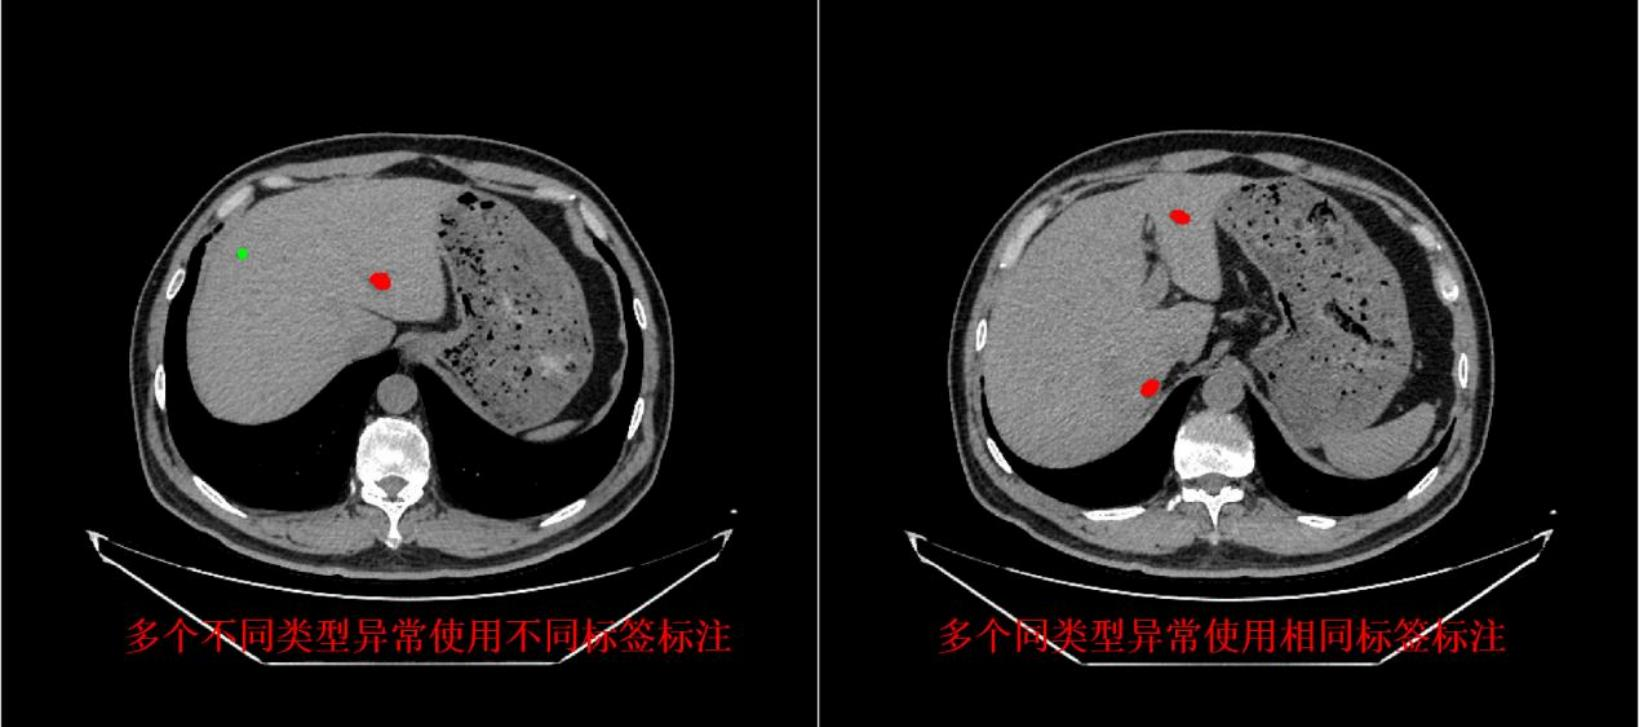

智慧医疗解决方案

面向医疗影像、辅助诊断、健康管理等领域,提供临床级的高质量医疗数据服务。

智慧医疗

面向医疗影像、辅助诊断、健康管理等领域,提供高质量医疗数据服务

• 医学影像数据